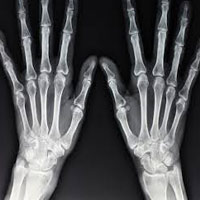

X-rays are routinely used for diagnosis of various bone fractures and bone diseases.

They play an important role in diagnosis of types of fractures and their further management.